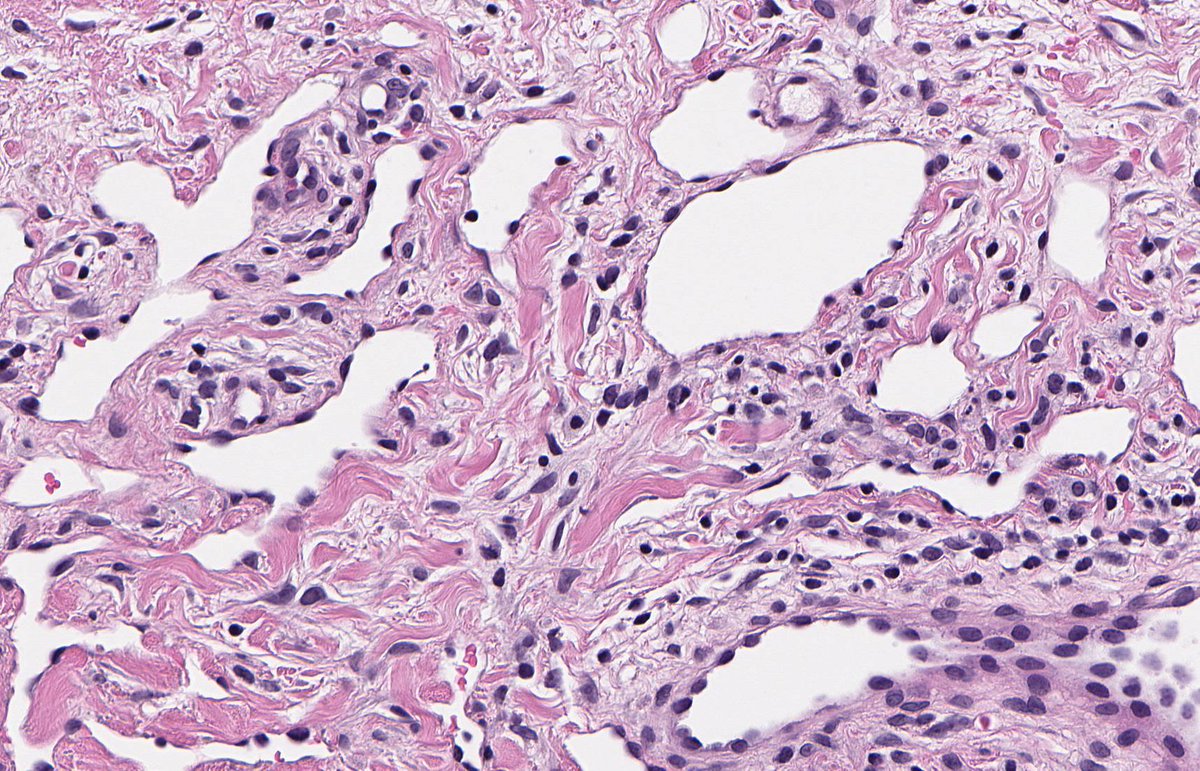

MASSIVE LOCALIZED LYMPHOEDEMA. NB: lobules of mature adipose tissue; expanded interlobular septa; spindle-stellate cells with mild atypia and prominent myxoid background; ectatic lymphatic spaces; MDM2 non-amp; typically occurs in context of morbid obesity (PMID: 9777990).

3

12

30